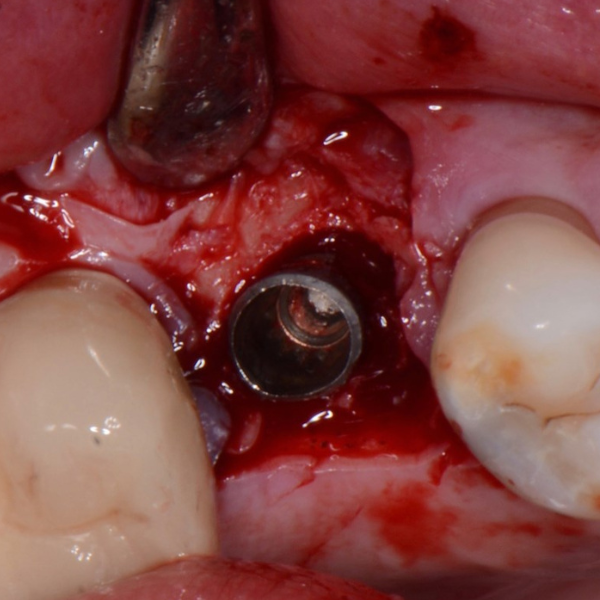

Removal Of Implant, Sinus Lift And Implant Replacement